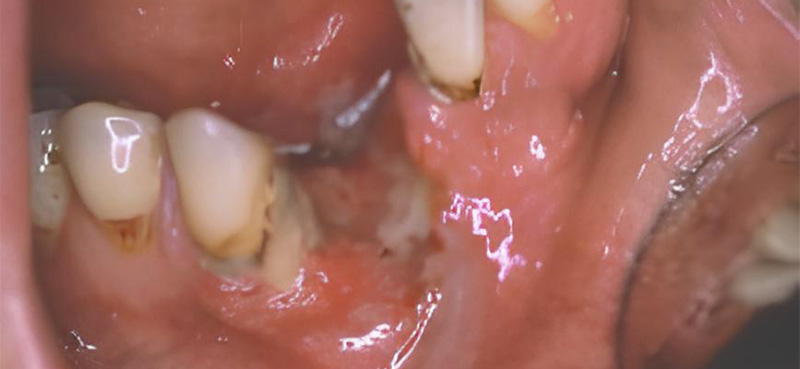

Fig. 04 : leucoplasie qui a dégénéré en cancer